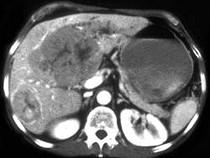

女,67岁,右上腹疼痛,消瘦四月余,CT检查如图,最可能的诊断是()A.肝血管瘤B.肝脓肿C.肝癌D.肝转移瘤E.肝囊肿

问题 女,67岁,右上腹疼痛,消瘦四月余,CT检查如图,最可能的诊断是()

选项 A.肝血管瘤 B.肝脓肿 C.肝癌 D.肝转移瘤 E.肝囊肿

答案 C